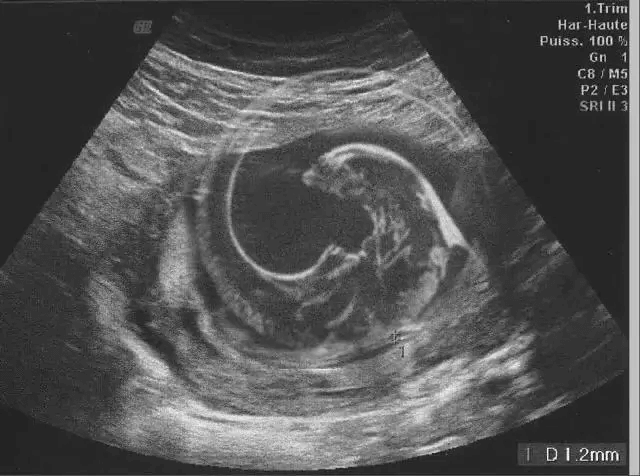

4. The Ultrasound Prank "Congrats! It's a... Dinosaur?!"

This couple was extremely excited to welcome their first child, and every doctor’s appointment was an exciting moment to see and hear their tiny baby. One time, after they did an ultrasound, the husband took a photo of it so they could send it to their families and friends.

Instead of sending the real photo, however, the husband began sending this ultrasound of a xenomorph to everyone, and when his wife realized, well, we can just imagine how amused she was (or not).